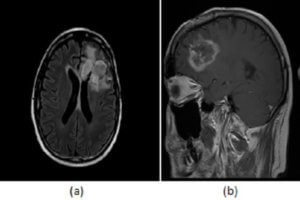

Radiation Necrosis

Radiotherapy is commonly used as an adjuvant therapy to surgery and chemotherapy in the management of primary brain neoplasms. Radiation destroys cells and damages the tumor blood supply. Addition of radiation therapy... Read more »

Residual/Recurrent Tumor

Imaging plays an important role in the diagnosis and management of patients with primary brain neoplasms. In particular, imaging is typically performed within 48 hours of tumor resection. Read more »